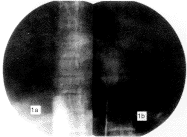

1.2 手术方法 2例病人均采用Seldinger法(经皮穿刺置管)穿刺右股静脉成功后,从穿刺内引入导丝,退出穿刺针,在电视监视下,将造影导管沿导丝送入狭窄下方,退出导丝造影(见封三图1a),明确腔静脉狭窄的类型及有无肝静脉狭窄,再将导丝通过狭窄插入右房,在狭窄上方造影(见封三图1b),进一步明确病变。造影完毕后,即可行扩张术。经造影导管置入交换导丝,退出造影导管,用不同型号扩张管依次扩张股静脉后再置入防漏扩张管鞘套,退出交换导丝,从鞘套内插入扩张导管(ONV 8.5-38-100-20-4.0,美国Cook公司生产)至狭窄部位,注入76%复方泛影葡胺充胀球囊,根据显影情况调整球囊位置,使其中部恰位于狭窄部位,再加压充胀球囊至束缚球囊的狭窄环消失,维持张力30 s左右,如此反复进行,直至隔膜已完全扩开再将导管退至原狭窄下方造影观察扩张效果。拔管后穿刺处加压包扎卧床休息6~12 h。术中间歇从导管内注入肝素盐水以防形成血栓。术后予抗凝药口服及对症处理。

3.2 分型及术式选择 布加综合征根据造影所见可大略分成节段性和隔膜型下腔梗阻,该两型又可根据有无肝静脉狭窄再分为两型。治疗上对节段性梗阻大多采用在直视下施行各种根治矫正术[2],本组1例节段性梗阻不伴有肝静脉狭窄患者曾试行球囊扩张术未获成功。但近年来有报道采用球囊扩张和静脉内支撑方法治疗节段性下腔静脉梗阻获得较好疗效[3]。对隔膜型狭窄治疗方法既往采用经右房直接撕裂法或体外循环下直视切除或成形术。现多采用介入治疗法,该方法的典型适应证为肝静脉通畅,无血栓形成的下腔静脉隔膜样狭窄[4]。两相比较,球囊导管撕裂法具有创伤小,相对安全,即时通过造影便可观察到手术效果,病人术后恢复快,住院时间短,费用较少等优点。治疗中我们将常规由上、下腔静脉分别造影改进为单由下腔静脉行狭窄上、下方造影(见封三图1a,1b),只要导管位置恰当,造影效果同样满意,并将造影和扩张一并进行,这样就简化了操作程序,减少了病人痛苦。

图1a 在狭窄下方造影,腔静脉呈 图1b 狭窄上方造影,位于同一椎

锥状改变无造影剂进入右房 间盘水平,和1a影像吻合